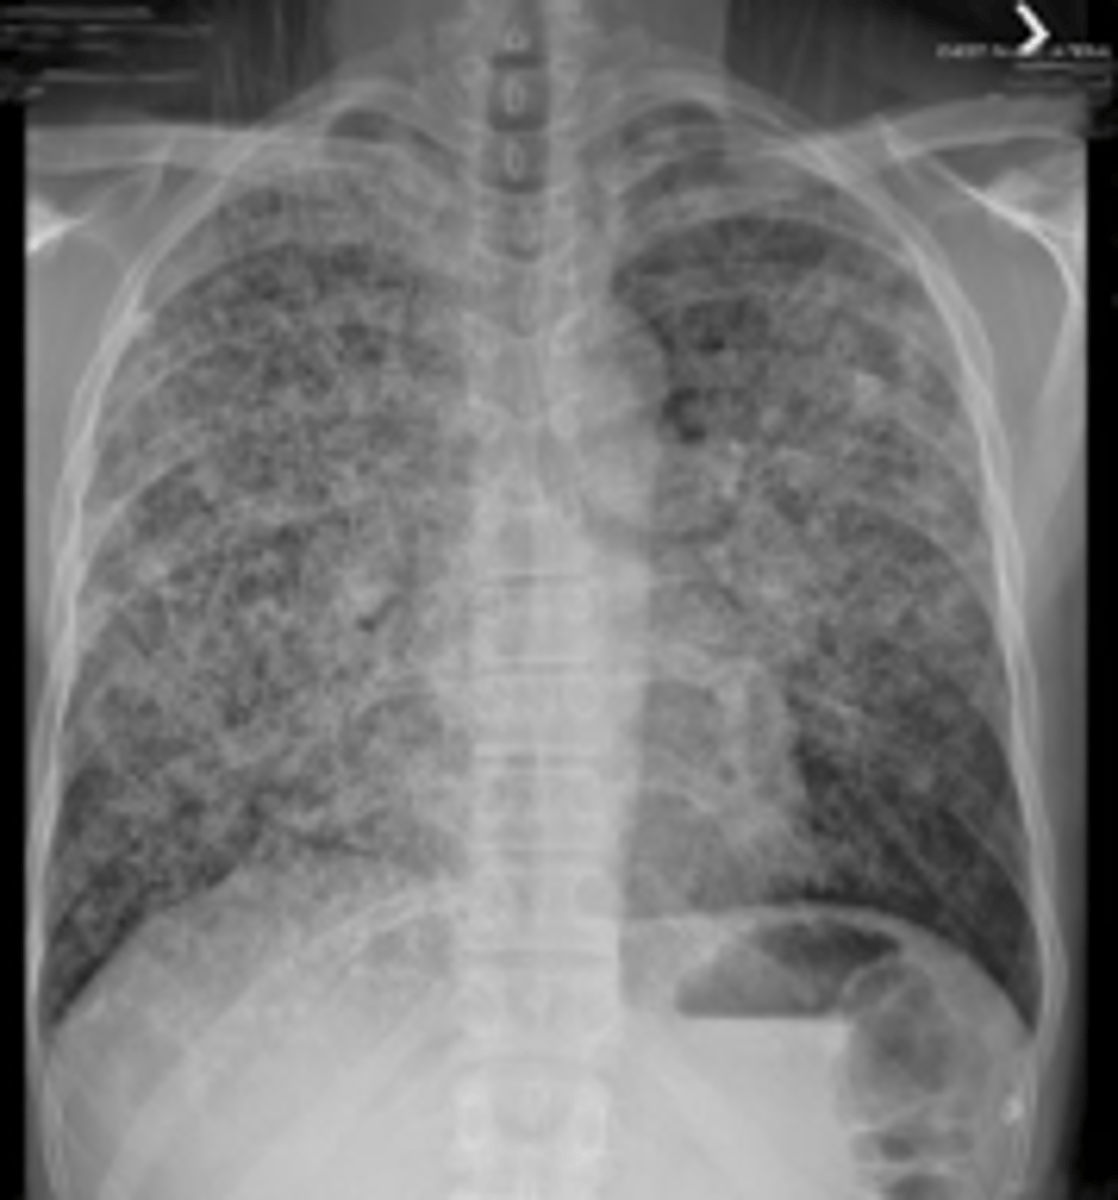

43

New cards

What will metastatic dz look like on radiograph?

Nodular pattern resulting from multiple small metastases to the lung from a colonic adenocarcinoma

<p>Nodular pattern resulting from multiple small metastases to the lung from a colonic adenocarcinoma</p>